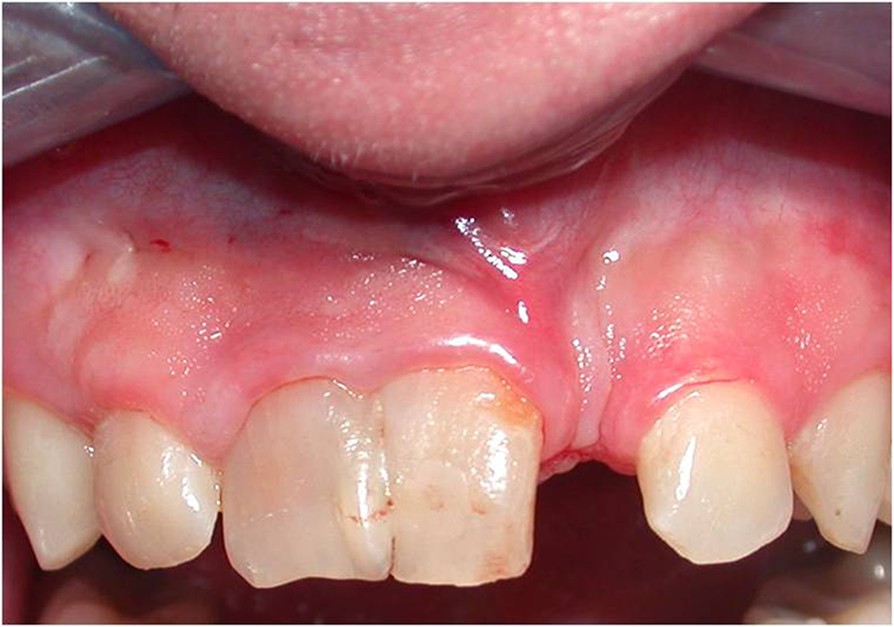

The Permanent Maxillary Incisors (Dental Anatomy, Physiology and Fused Incisors intraoral examination revealed that a permanent maxillary left lateral incisor was fused with a supernumerary tooth. The fused tooth had a broad. The main management of this clinical condition is. fusion is a developmental anomaly defined as the union of two adjacent tooth germs at the dentin level. the data disclosed the occurrence of double teeth in. Fused Incisors.

Multidisciplinary approach to fused maxillary central incisors a case Fused Incisors intraoral examination revealed that a permanent maxillary left lateral incisor was fused with a supernumerary tooth. primary fused teeth (pft) are more frequently observed in primary than in permanent dentition. fusion is a developmental anomaly defined as the union of two adjacent tooth germs at the dentin level. this paper summarizes the treatment methods for fused. Fused Incisors.

Esthetic management of fused incisors with ceramic veneers Journal of Fused Incisors this report discusses two cases involving the multidisciplinary management of permanent maxillary left. fusion is a developmental anomaly defined as the union of two adjacent tooth germs at the dentin level. intraoral examination revealed that a permanent maxillary left lateral incisor was fused with a supernumerary tooth. The fused tooth had a broad. The main management of. Fused Incisors.